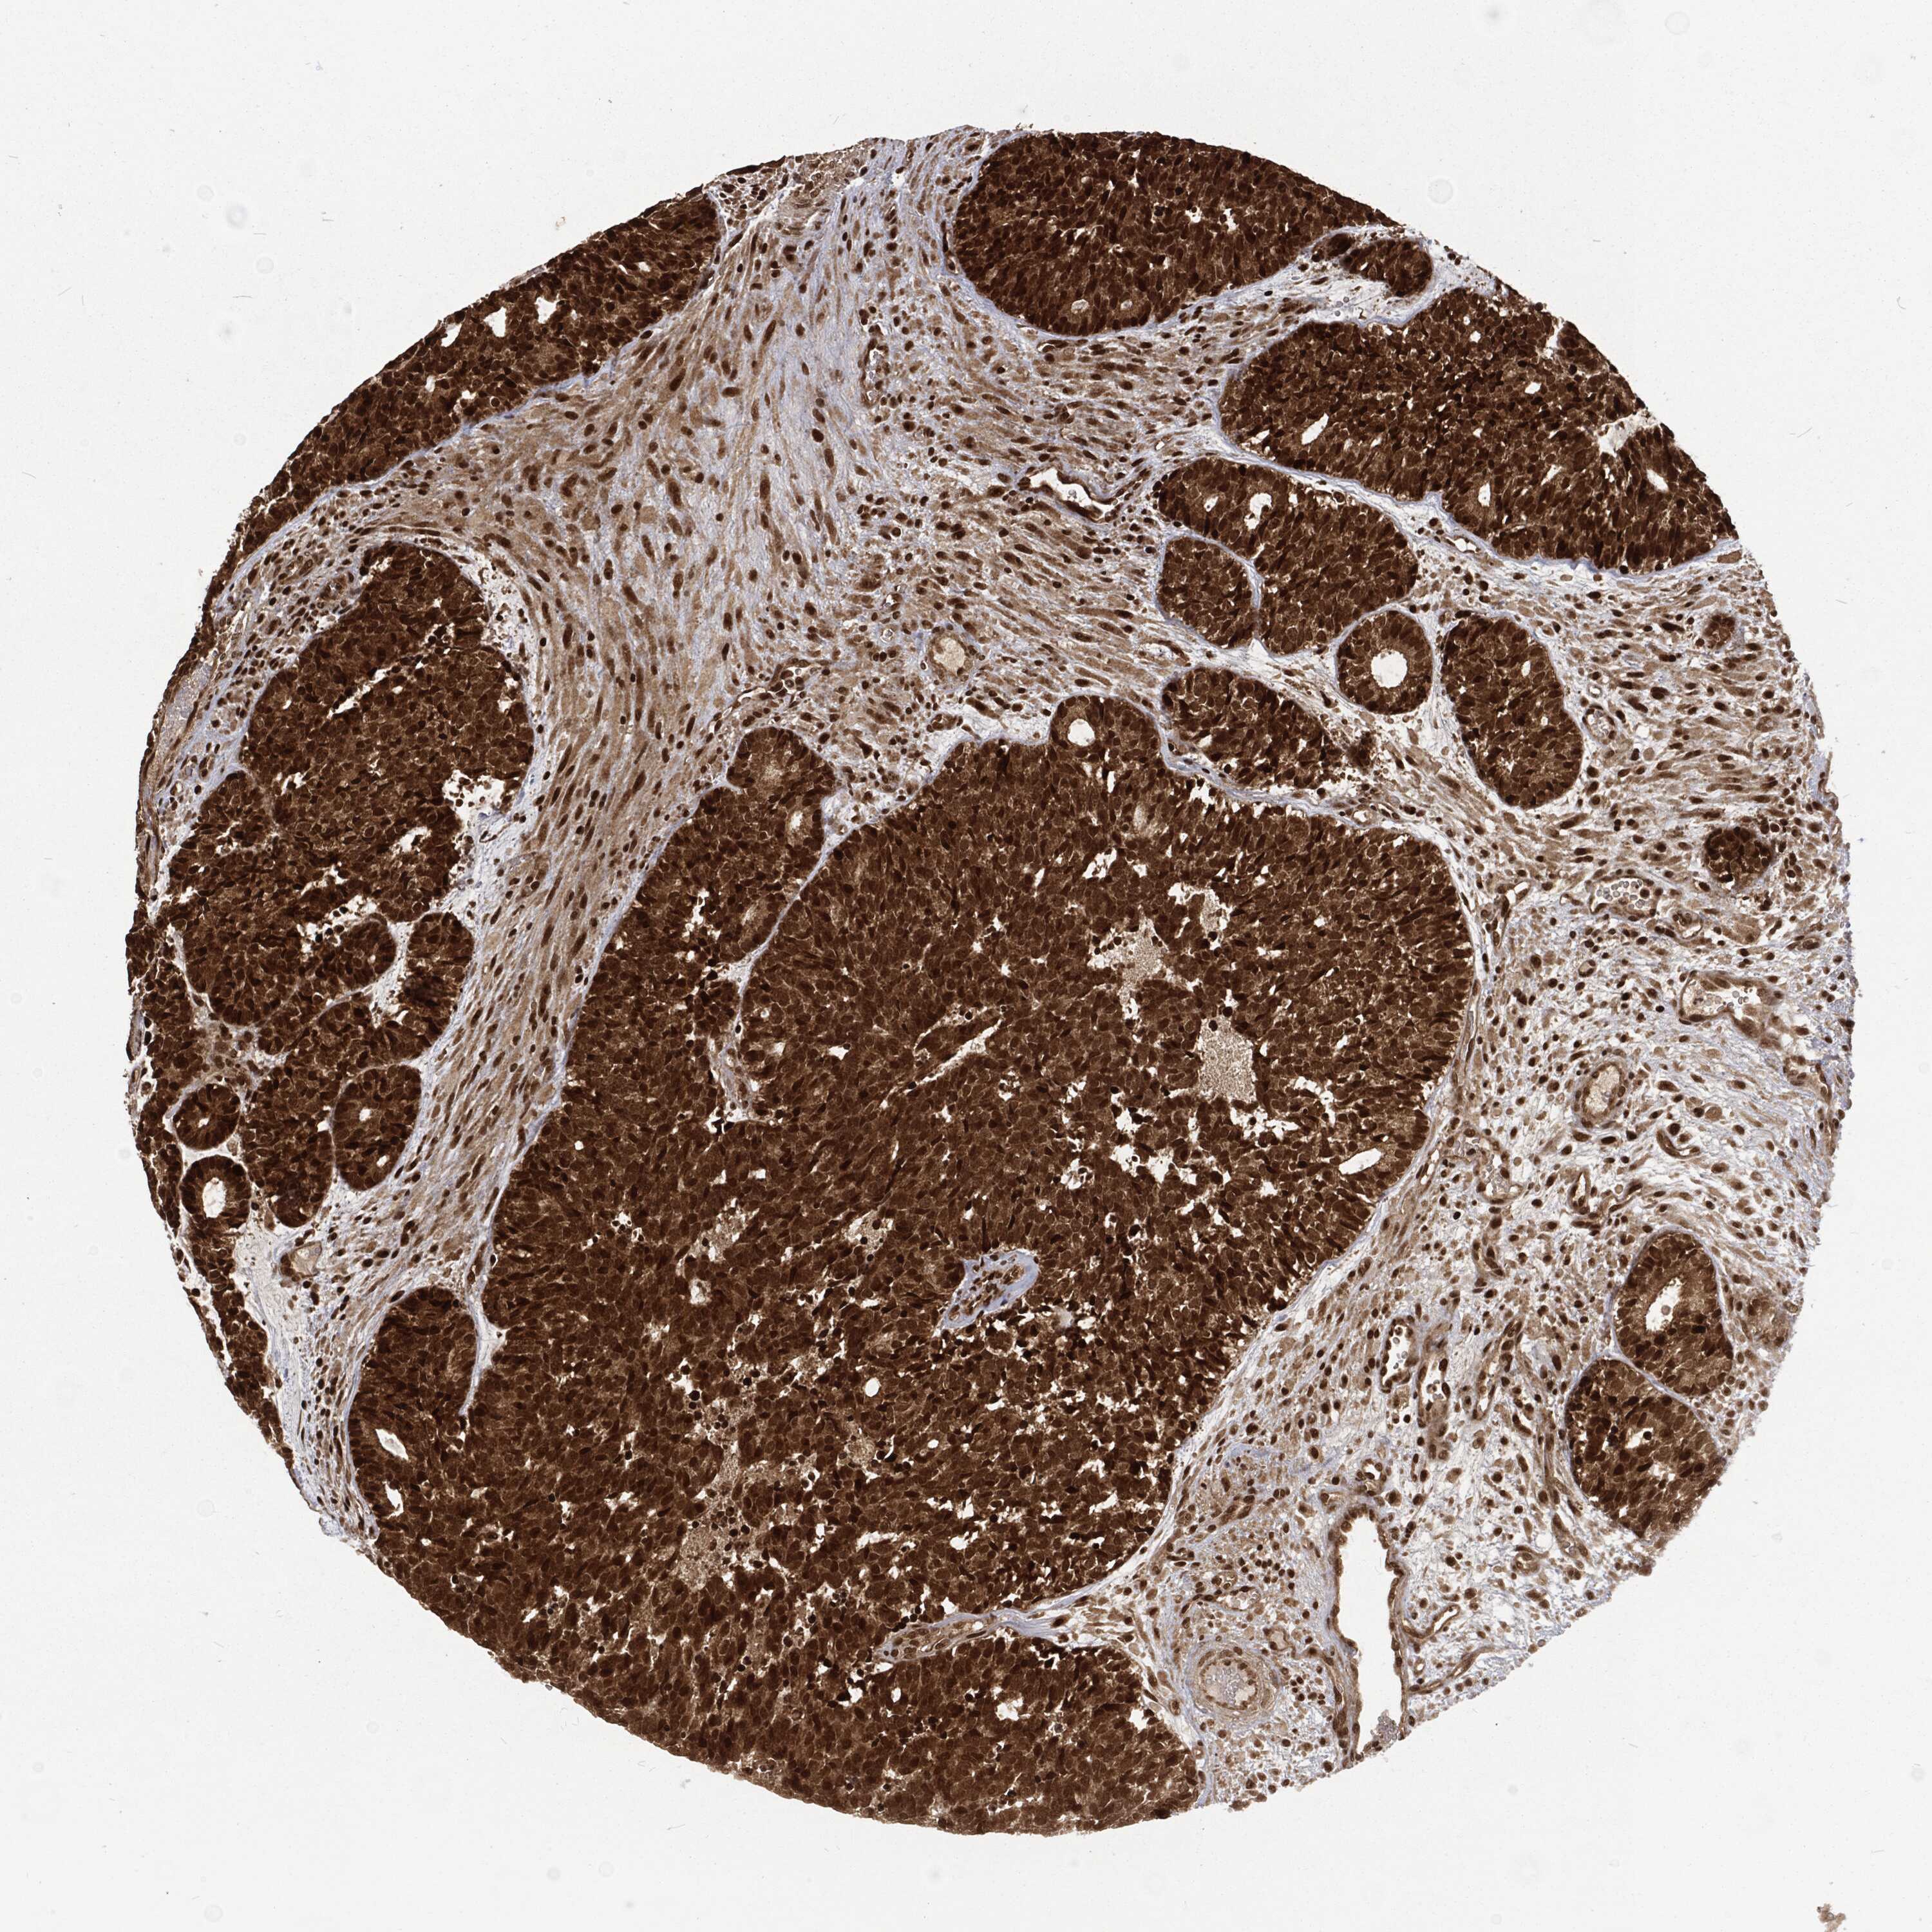

HEAD AND NECK CANCER - Protein expressioni

A mouse-over function shows sample information and annotation data. Click on an image to view it in a full screen mode. Samples can be filtered based on level of antibody staining by selecting one or several of the following categories: high, medium, low and not detected. The assay and annotation is described here.

Antibody stainingi

Antibody staining in the annotated cell types in the current human tissue is reported as not detected, low, medium, or high, based on conventional immunohistochemistry profiling in selected tissues. This score is based on the combination of the staining intensity and fraction of stained cells.

Each image is clickable and will lead to virtual microscopy that enables deeper exploration of all samples and also displays staining intensity scores, fraction scores and subcellular localization as well as patient and tissue information for each sample.

Antibody HPA041367

Staining

High

Medium

Low

Not detected

Intensity

Strong

Moderate

Weak

Negative

Quantity

>75%

75%-25%

<25%

None

Location

Nuclear

Cytoplasmic/membranous

Cytoplasmic/membranous,nuclear

Squamous cell carcinoma, NOS